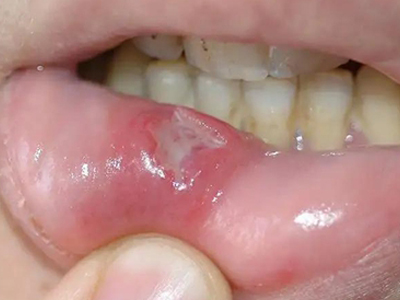

重型阿弗他溃疡下唇内长溃疡图

重型阿弗他溃疡患者下唇内黏膜有一个黄豆大小的溃疡面,表面覆盖一层黄白色的假膜,周围组织红肿、隆起,患者感觉患处疼痛感剧烈。